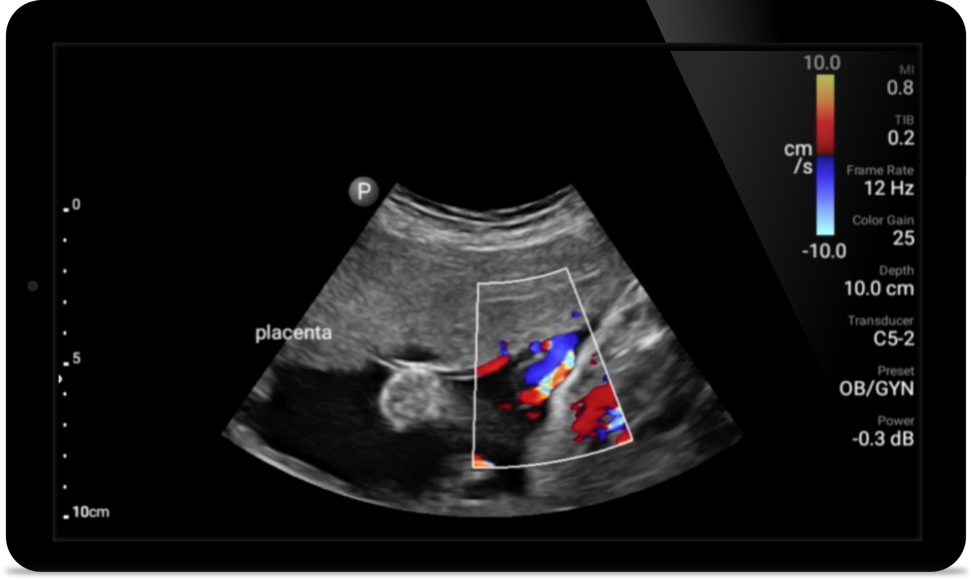

Lumify S4-1 broadband phased array transducer

• 4 to 1 MHz extended operating frequency range • 2D, color Doppler, M-mode, advanced XRES and multivariate harmonic imaging • High-resolution imaging for abdominal and cardiac applications: Cardiac, OB/GYN, Lung, Abdomen and FAST imaging preset optimizations Lumify aids life-saving technology in prehospital setting